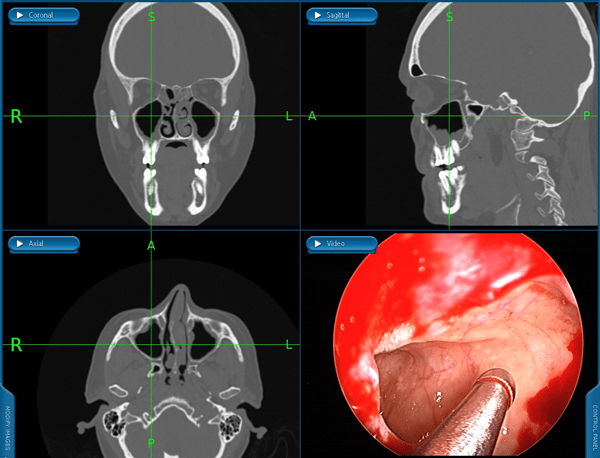

A dra Cynthia avalia em consulta médica, relacionando o desvio aos sintomas. Pois apenas a presença de um desvio de septo não significa que seja necessário operar. É fundamental estabelecer a relação dele com o causa dos sintomas: obstrução nasal, cefaléia, ronco, sinusite de repetição.

Pode ser necessário tomografia de nariz ou video naso fibroscopia

A septoplastia é realizada com anestesia e técnica minimamente invasiva. O objetivo é melhorar a respiração, preservar estruturas importantes e garantir um pós-operatório mais tranquilo. Na maioria das vezes pode ser realizada sob visão endoscópica e quando há necessidade de redução dos cornetos nasais, é realizada a turbinectomia por radiofrequência, técnica mais segura que permite recuperação mais confortável.